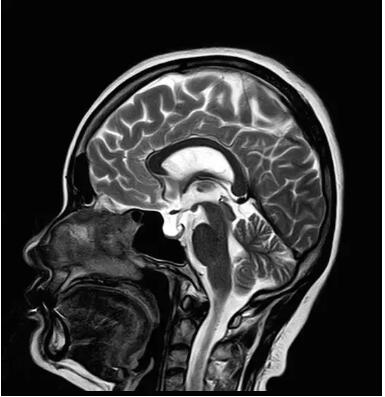

1.鍍膜新磁體

磁體系統(tǒng)是磁共振成像的核心部件之一,磁體所產(chǎn)生的主磁場(chǎng)是磁共振成像的基礎(chǔ)。高均勻度的主磁場(chǎng)是保證MR信號(hào)空間準(zhǔn)確性的前提,直接影響成像質(zhì)量。高均勻度的主磁場(chǎng)可以帶來更好的圖像質(zhì)量、更大的掃描視野、更均勻的壓脂效果。特別是在壓脂、偏中心掃描成像、磁敏感等常見應(yīng)用中,高均勻度的主磁場(chǎng)可以幫助提升此類應(yīng)用的成像質(zhì)量。

隨著患者對(duì)磁共振掃描的舒適度要求越來越高,磁體越來越短,開放度越來越高,這對(duì)提高磁場(chǎng)均勻度又帶來了新的挑戰(zhàn)。采用短磁體的設(shè)計(jì)獲得更高舒適度的同時(shí),保證最好的磁場(chǎng)均勻度,并獲得最佳的成像效果,是所有磁共振廠家的共同目標(biāo)。

Pure Elan磁共振的磁體采用佳能公司獨(dú)有的高密度薄層鍍膜貼合技術(shù),增加超導(dǎo)線圈組數(shù), 實(shí)現(xiàn)線圈超高密度環(huán)繞,與傳統(tǒng)1.5T磁共振產(chǎn)品6組超導(dǎo)線圈設(shè)計(jì)相比,鍍膜磁體采用業(yè)內(nèi)最高水平的9組超導(dǎo)線圈設(shè)計(jì),獲得更好的磁場(chǎng)均勻度,達(dá)到了業(yè)界1.5T開放孔徑磁共振領(lǐng)域最好的磁場(chǎng)均勻度。采用業(yè)內(nèi)領(lǐng)先的1.4米短磁體開放孔徑設(shè)計(jì),55cm大視野掃描,給予患者更開放的空間感以及更舒適的掃描體驗(yàn)。